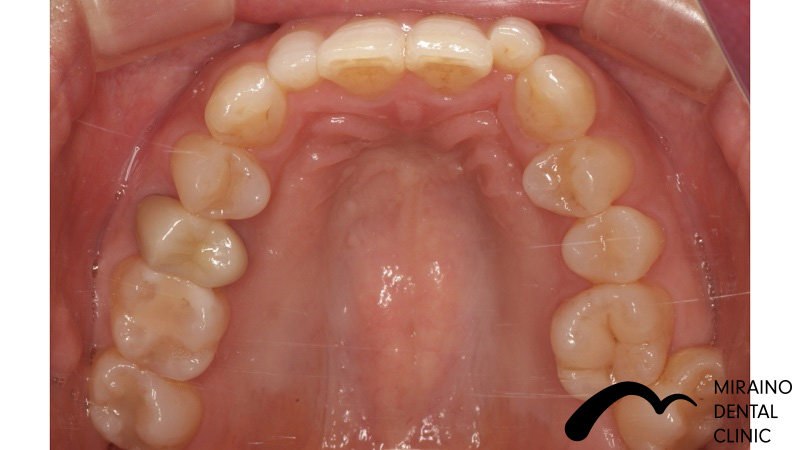

被せ物&詰め物・メタルフリークラウン&インレーの症例

| 施術名 | 被せ物・メタルフリークラウン |

| 施術の概要 | 銀歯のところから変な匂いがするということで来院されました。 5年以上前に治療してもらった歯科医院では「銀歯による虫歯治療のデメリット」を 聞いたことがなかったとのこと、でした。 銀歯が大きく歯が割れてしまうリスクが高く、次に再発した際は神経を取らないといけなくなる可能性が高いため、 なるべく再発しにくい歯科治療を希望され、汚れのつきにくい素材[ジルコニアセラミック]で被せ物を装着しました。 |

クリックして詳細を表示

| 施術の内容 | 根っこの治療後など歯の表面を削って強度の高く、汚れの付きにくいジルコニアクラウンを被せて歯を補強します。 |

| 1歯あたりの治療費 | 80,000~150,000円 |

| 施術名 | 詰め物・メタルフリーインレー |

| 施術の概要 | 銀歯のところから変な匂いがするということで来院されました。 5年以上前に治療してもらった歯科医院では「銀歯による虫歯治療のデメリット」を 聞いたことがなかったとのこと、でした。 銀歯が大きく歯が割れてしまうリスクが高く、次に再発した際は神経を取らないといけなくなる可能性が高いため、 なるべく再発しにくい歯科治療を希望され、汚れのつきにくい素材[ジルコニアセラミック]で被せ物を装着しました。 |

クリックして詳細を表示

| 施術の内容 | 銀歯は歯より硬すぎる、歯を腐食させる作用があることから約5年で再発すると言われています。 ラバーダムを用いて唾液による接着不良のリスクを排除し完全に水分を排除した状態でムシ歯治療を行います。 型取りを行い、技工士によって汚れの付きにくいセラミックで形を再現している |

| 1歯あたりの治療費 | 1歯:50,000円 |